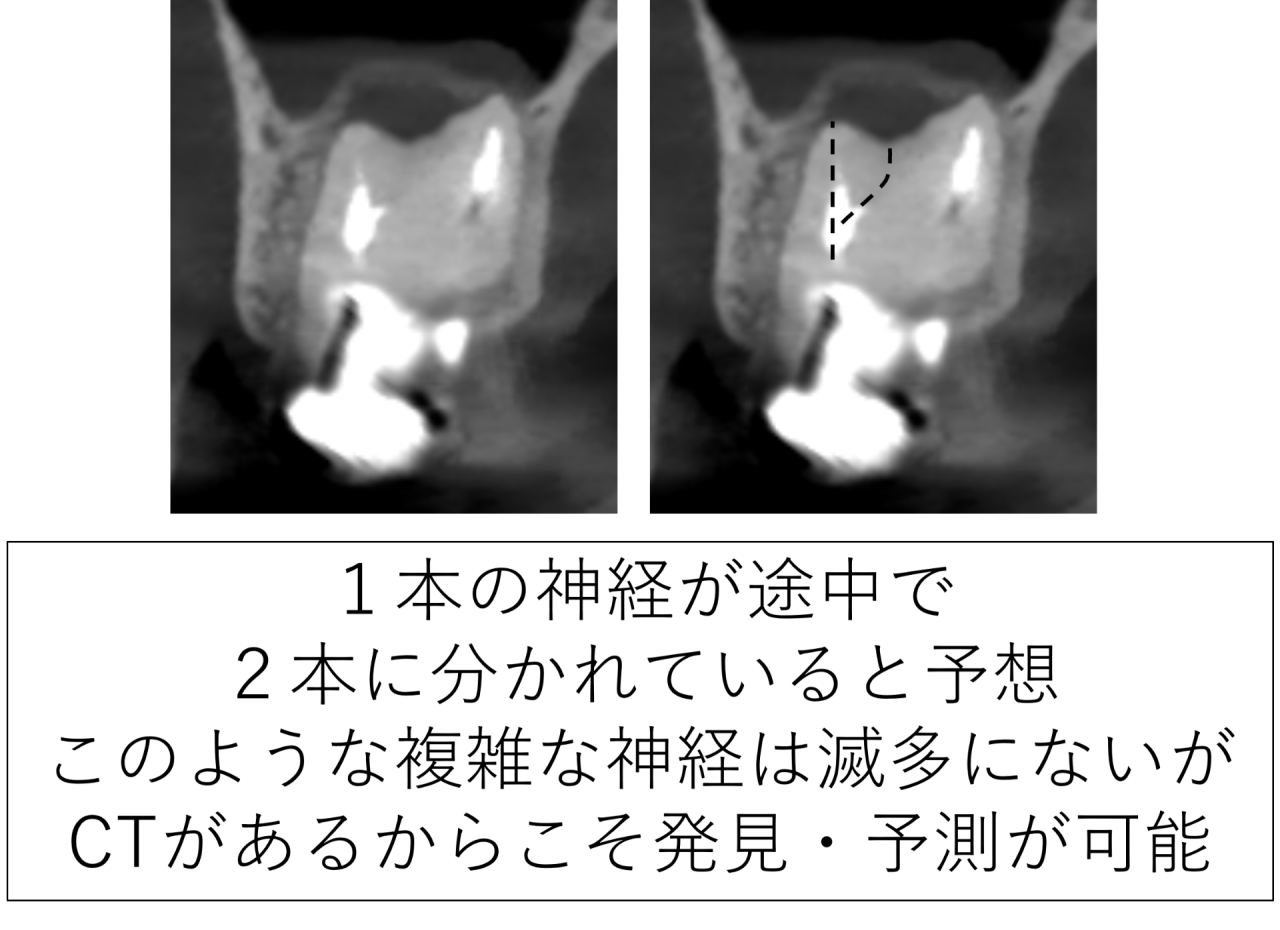

奥歯の神経は一本ではなく、複雑に枝分かれしています

歯の神経は単純な一本の管ではありません。特に奥歯では、細い通り道が枝分かれしていることが多くあります。

今回の歯は、その枝分かれが非常に複雑でした。通常の形とは異なり、1つの神経が途中で2つに分かれていました。このような形態では、治療時に見落としが起こりやすくなります。事前のCTで予測していたからこそ発見ができます。顕微鏡(マイクロスコープ)とCTの無い根管治療が失敗する確率の高い理由です。

枝分かれした部分に神経や感染組織がわずかに残っているだけでも、そこが細菌の温床となり、炎症が持続します。その結果、根の先で骨の吸収が進行します。